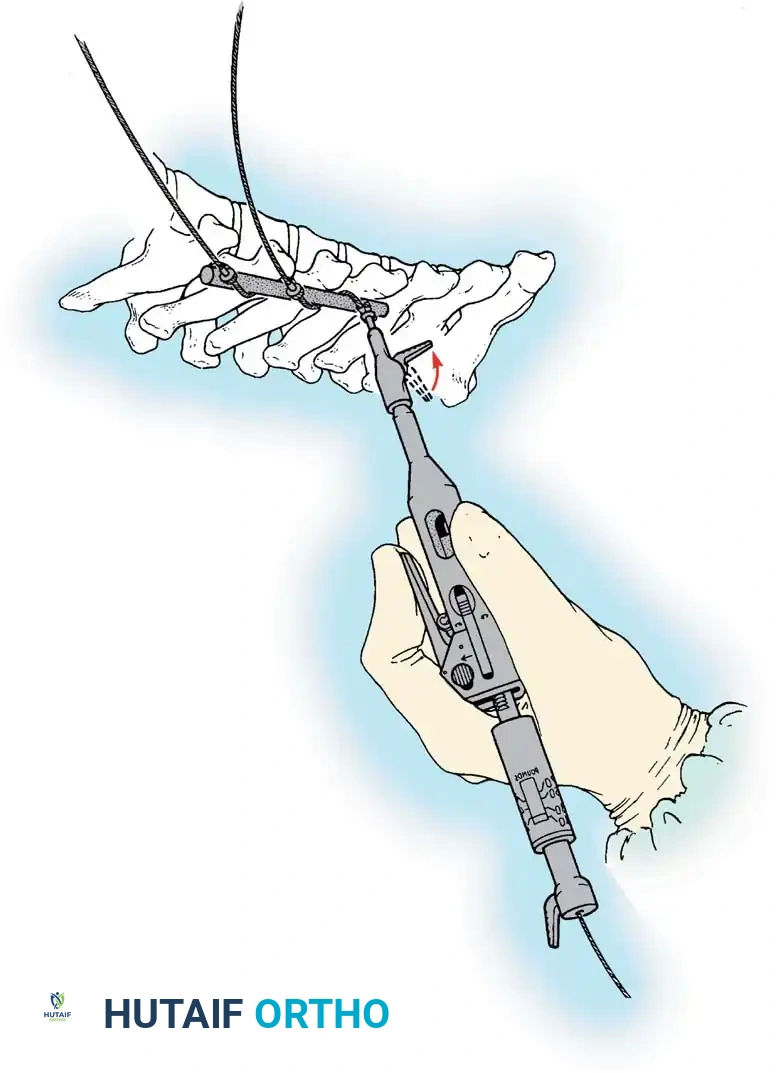

The Hall Technique

The Hall technique offers an alternative method for facet obliteration and grafting, particularly useful in rigid deformities.

Fig. 38-28: The Hall technique of facet fusion, involving sharp excision of the inferior facet and trough creation.

- Sharply amputate the inferior articular facet with a gouge and remove the bone fragment entirely. This exposes the cartilage of the superior facet.

- Remove the exposed cartilage completely with a sharp curet.

- Create a bleeding trough by removing the outer cortex of the superior facet.

- Impact cancellous bone grafts directly into this vascularized trough.

- Complete the procedure with global decortication of the posterior elements.